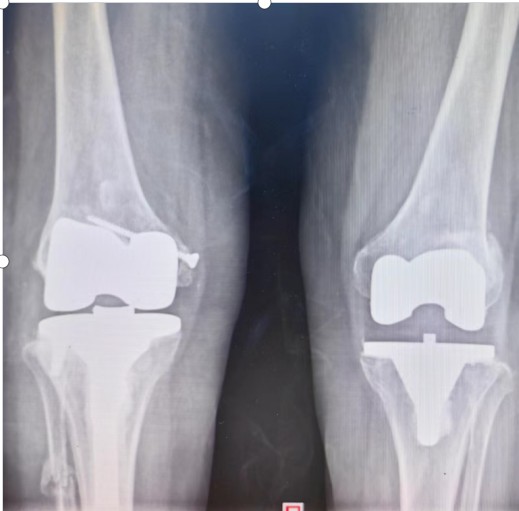

羅湘平主任醫(yī)師團(tuán)隊(duì)考慮患者的家庭經(jīng)濟(jì)狀況,決定力爭修復(fù)患者原有的解剖結(jié)構(gòu),避免使用更多的人工替代品,以減少患者的經(jīng)濟(jì)負(fù)擔(dān)。為了能夠順利完成手術(shù)、達(dá)到滿意的效果,羅湘平主任醫(yī)師做好充分的術(shù)前準(zhǔn)備工作,精心設(shè)計(jì)手術(shù)方案,選擇為患者實(shí)施普通的人工膝關(guān)節(jié)置換,內(nèi)側(cè)副韌帶止點(diǎn)采用螺絲重建術(shù)恢復(fù)膝關(guān)節(jié)穩(wěn)定性,脛骨外側(cè)平臺(tái)骨缺損采用螺絲釘加骨髓泥充填,為患者節(jié)省3萬余元材料費(fèi)。劉奶奶的膝關(guān)節(jié)畸形得到矯正、恢復(fù)了穩(wěn)定性,于術(shù)后第10天順利出院。

術(shù)前

術(shù)后